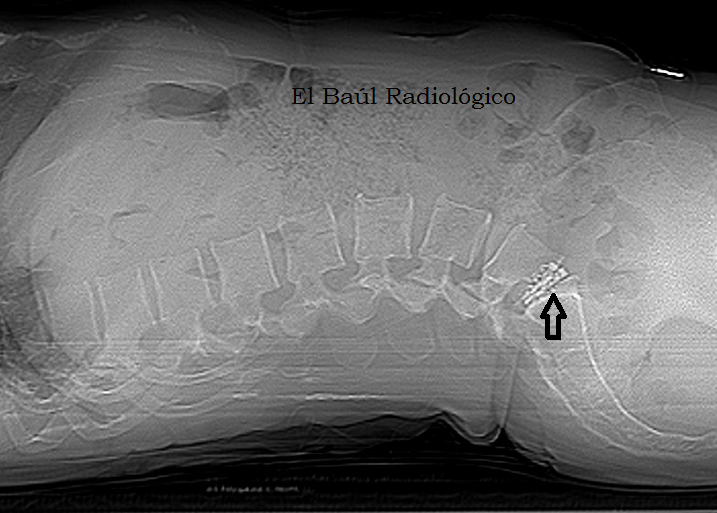

Перелом 12 грудного позвонка

3.Back pain and decreased anal sphincter tone after motor accident. Left panel: Acute fracture of the 12th thoracic vertebra on CT. Right panel: Edema as a sign of acute fracture in the 12th thoracic vertebra on sagittal T2WI.